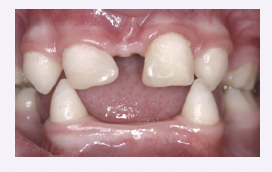

Cleft lip/palate

● Cleft lip results from the failure of the maxillary and medial nasal processes to fuse during the 4th – 7th

week of embryonic development

● Cleft palate occurs when the palatal shelves fail to fuse, typically between the 8th – 12th week of gestation

● Higher frequency of cleft lip and/or palate seen in Pierre Robin sequence, Treacher Collins syndrome, fetal

alcohol syndrome, cleidocranial dysplasia, and nevoid basal cell carcinoma

● Genetic and environmental factors play a role (e.g., maternal smoking, alcohol, folic acid deficiency)